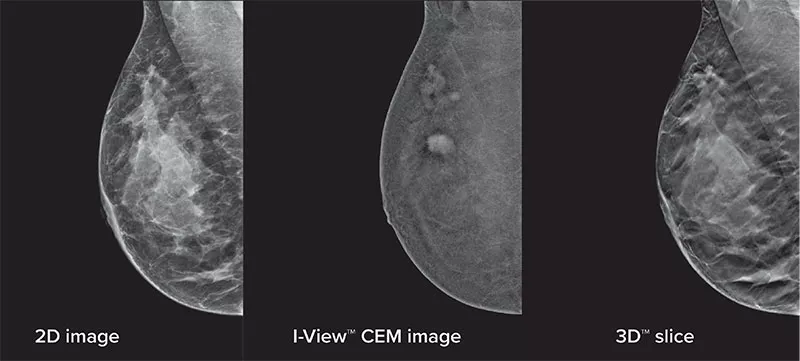

Eliminates Structural Background

Acquire a pair of high- and low-energy images in rapid succession. This allows for regions of abnormal blood flow to be displayed by subtracting the background breast parenchyma.

Contrast-enhanced mammography enhances visualization and may uncover hidden abnormalities – a crucial factor in reducing missed and or underdiagnosed cancers.